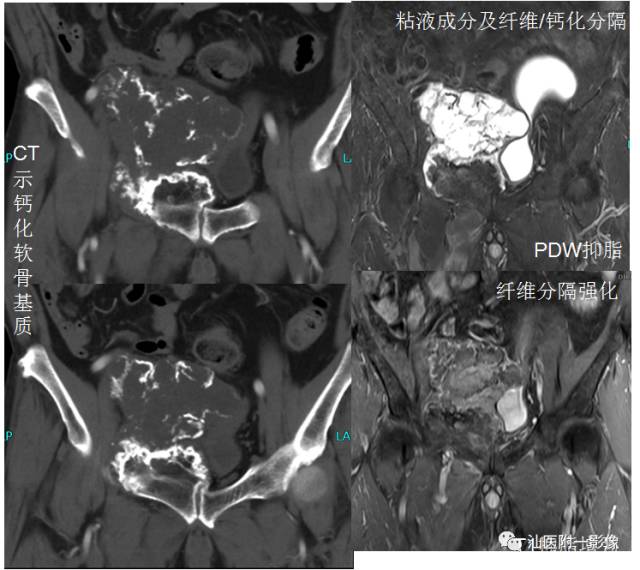

X线/CT:1.X线透亮的基质

3.环状、逗号状或点状、爆米花状钙化

MR:

T2WI高信号的肿瘤软骨被低信号的纤维间隔分隔成不规则的分叶状,其内或边缘夹有更低信号钙化影T1WI:多为不均匀等低混杂信号。增强主要为纤维间隔强化,瘤软骨强化不明显。